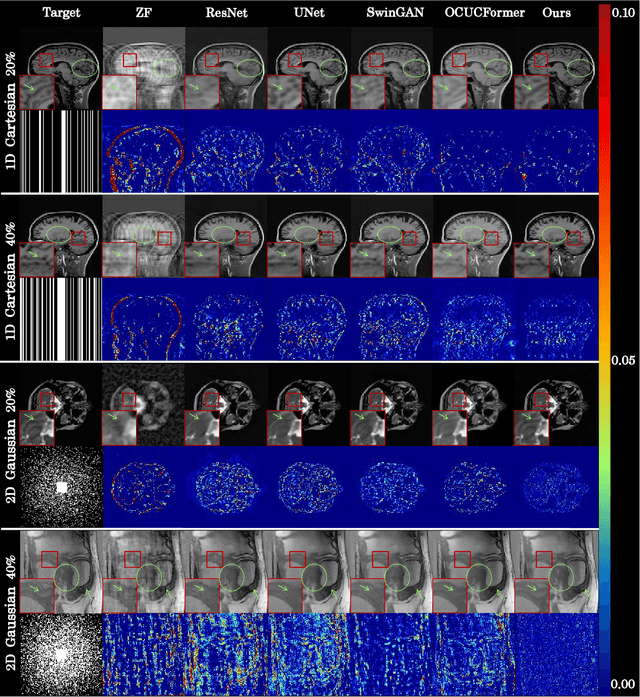

Abstract:The accelerated MRI reconstruction poses a challenging ill-posed inverse problem due to the significant undersampling in k-space. Deep neural networks, such as CNNs and ViT, have shown substantial performance improvements for this task while encountering the dilemma between global receptive fields and efficient computation. To this end, this paper pioneers exploring Mamba, a new paradigm for long-range dependency modeling with linear complexity, for efficient and effective MRI reconstruction. However, directly applying Mamba to MRI reconstruction faces three significant issues: (1) Mamba's row-wise and column-wise scanning disrupts k-space's unique spectrum, leaving its potential in k-space learning unexplored. (2) Existing Mamba methods unfold feature maps with multiple lengthy scanning paths, leading to long-range forgetting and high computational burden. (3) Mamba struggles with spatially-varying contents, resulting in limited diversity of local representations. To address these, we propose a dual-domain multi-scale Mamba for MRI reconstruction from the following perspectives: (1) We pioneer vision Mamba in k-space learning. A circular scanning is customized for spectrum unfolding, benefiting the global modeling of k-space. (2) We propose a multi-scale Mamba with an efficient scanning strategy in both image and k-space domains. It mitigates long-range forgetting and achieves a better trade-off between efficiency and performance. (3) We develop a local diversity enhancement module to improve the spatially-varying representation of Mamba. Extensive experiments are conducted on three public datasets for MRI reconstruction under various undersampling patterns. Comprehensive results demonstrate that our method significantly outperforms state-of-the-art methods with lower computational cost. Implementation code will be available at https://github.com/XiaoMengLiLiLi/DM-Mamba.